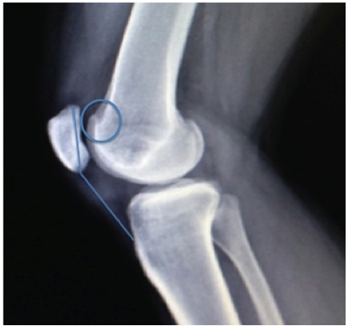

Knee radiograph evaluation (Figure 1 & 2) demonstrated a trochlear groove angle > 145º and type III patella according to the Wiberg classification as well as a crossing sign; there were no arthritic changes and no patella alta or baja; CT scan (Figure 3) showed femoral trochlea dysplasia, normal TT-TG, patella external translation and patella chondromalacia; MRI had the same findings as the CT and reported normal menisci and ligaments.

Figure 2 X-ray knee lateral view showing crossing sign (circle) and normal patella height by Insall-Salvati ratio (lines); no arthritic changes are seen.